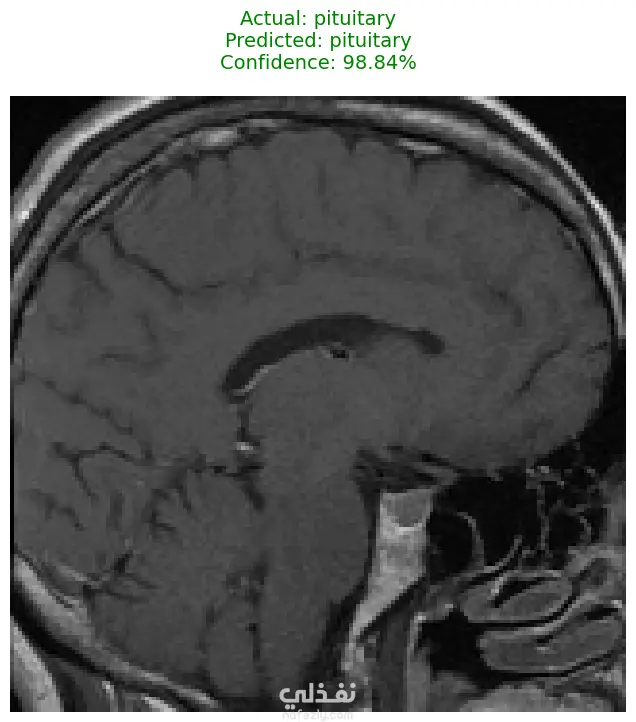

الوصف: قمت بتطوير نموذج تعلم عميق (CNN) قادر على التمييز بين 27 فئة مختلفة من الأورام والحالات الطبيعية بدقة تصل إلى 93%. شمل المشروع مراحل معالجة البيانات الضخمة، تنظيفها وموازنتها، وتصميم معمارية مخصصة لضمان الكفاءة العالية وتقليل استهلاك الذاكرة. المميزات التقنية: دقة استثنائية: حقق النموذج دقة تصل إلى 93% على بيانات التحقق (Validation Accuracy). معالجة البيانات الضخمة: تم العمل على قاعدة بيانات ضخمة، مع تطبيق استراتيجيات موازنة البيانات (Data Balancing) لضمان عدم انحياز الموديل. معمارية مخصصة: تم تصميم شبكة CNN تدعم تقنيات Batch Normalization لتسريع التعلم و Global Average Pooling لتقليل استهلاك الذاكرة وضمان استقرار النموذج. معالجة الصور: استخدام تقنيات OpenCV لقص الصور (Cropping) وإزالة الهوامش غير الضرورية لتركيز الموديل على منطقة الورم فقط. الأدوات والتقنيات المستخدمة: لغة البرمجة: Python. المكتبات الأساسية: TensorFlow / Keras. معالجة الصور: OpenCV & PIL. تحليل النتائج: Scikit-learn (Confusion Matrix & Classification Report). البيئة البرمجية: Google Colab (GPU Acceleration). النتائج المحققة: نموذج قادر على التعرف على أنواع نادرة من الأورام بدقة عالية. تقرير فني يوضح أداء الموديل لكل فئة (Precision & Recall). ملف نموذج جاهز للنشر (Deployment) بصيغة keras الحديثة. يمكنكم الاطلاع على الكود المصدري كاملاً والرسوم البيانية لتقييم أداء النموذج عبر رابط GitHub المرفق، كما يتوفر رابط تحميل النموذج المدرب داخل ملف الشرح.